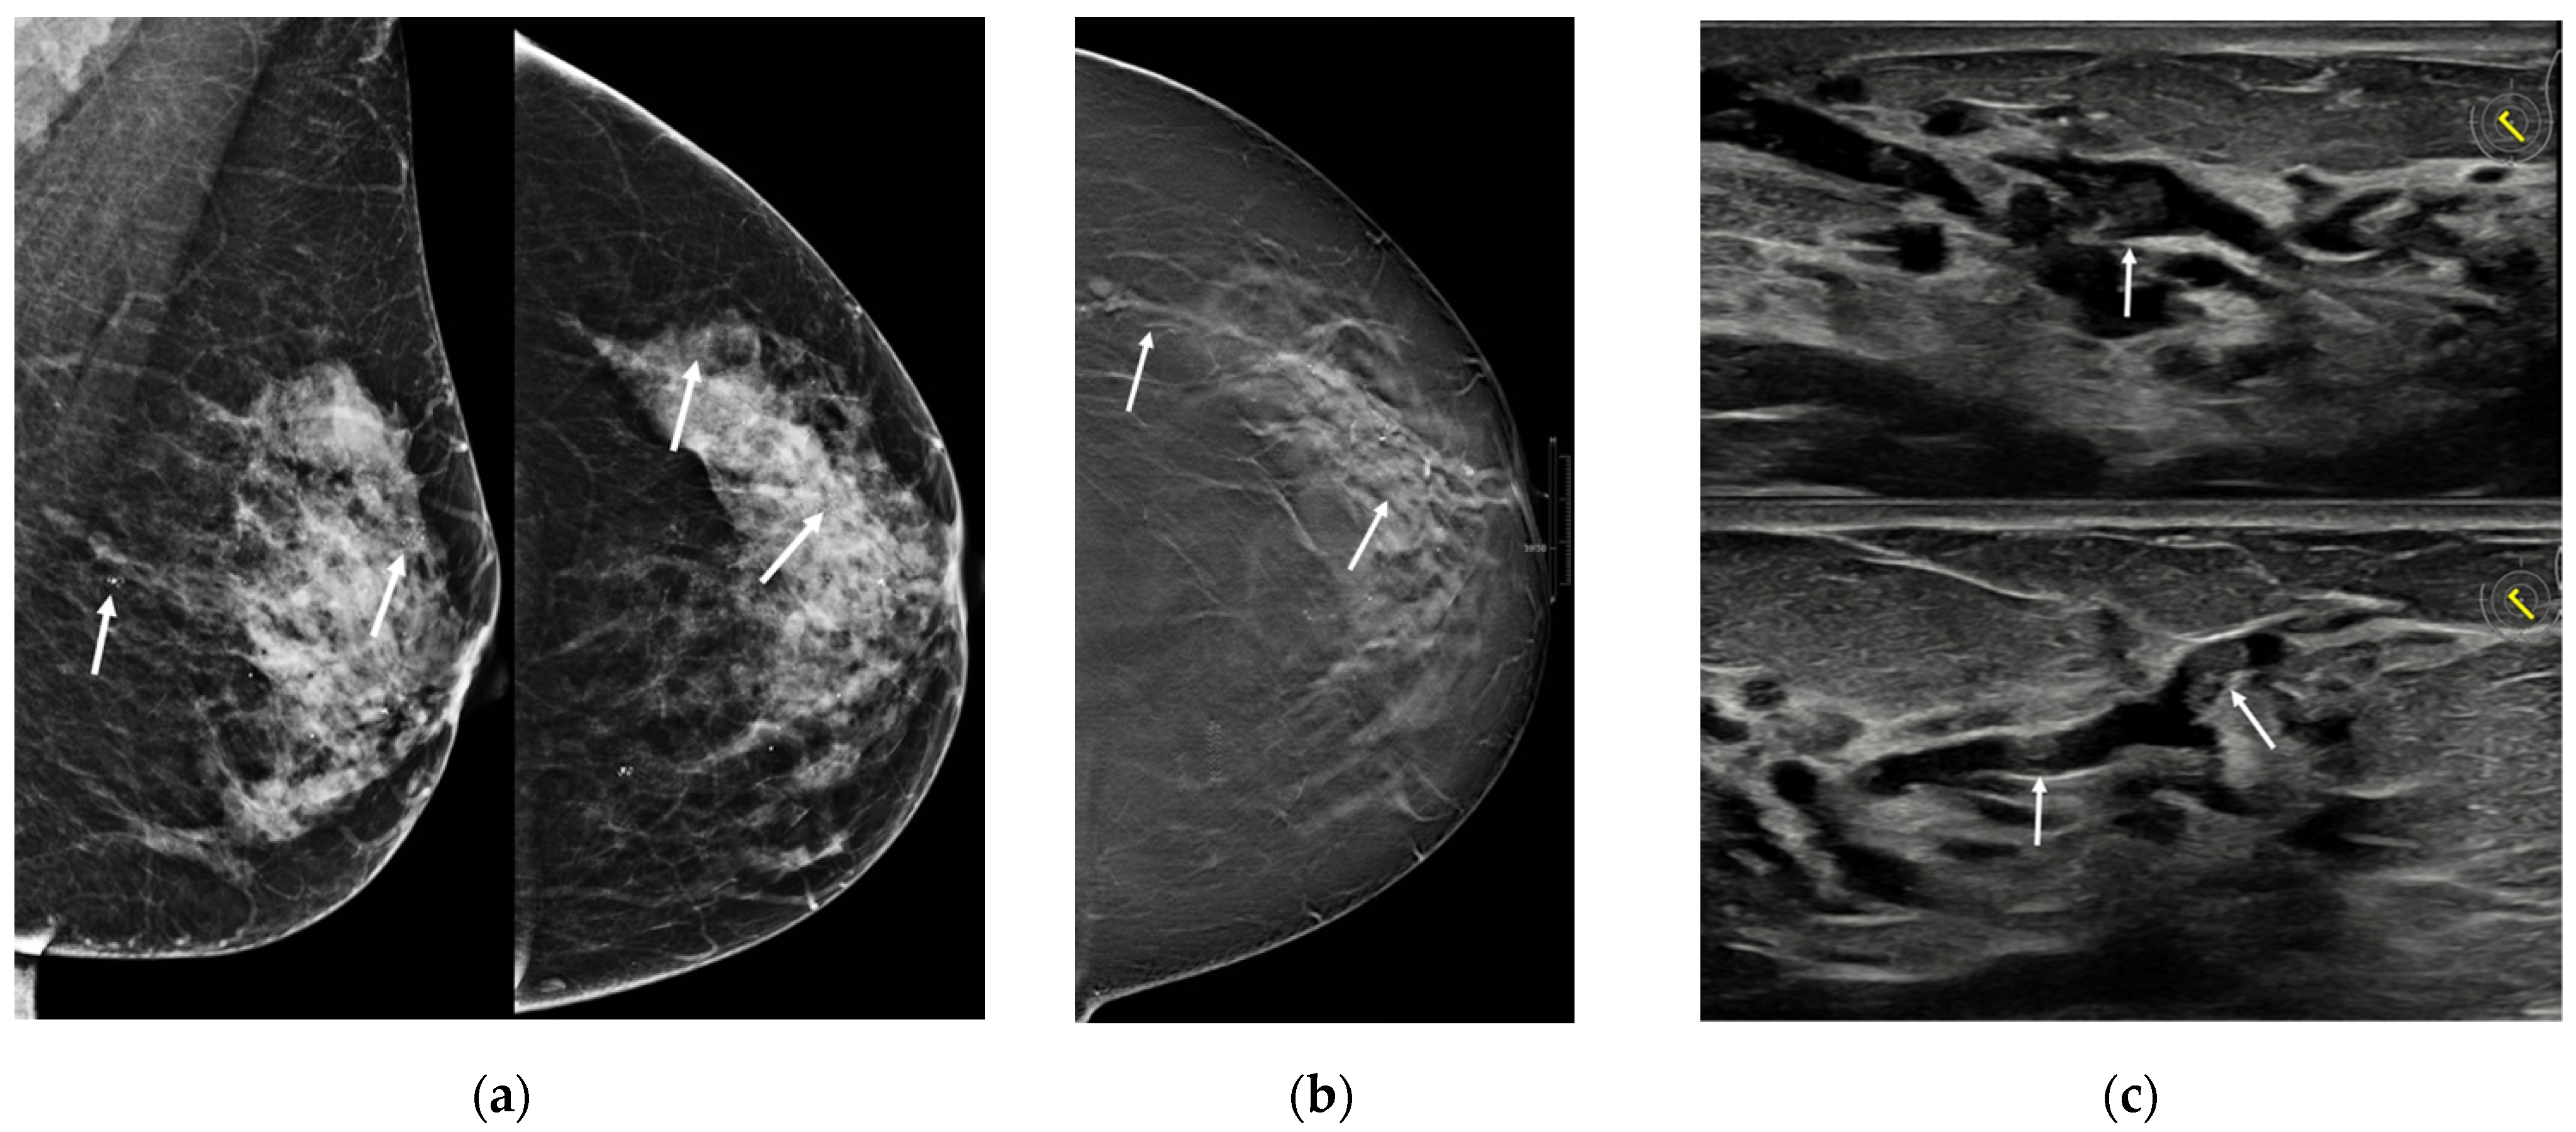

| Son 2009 [25] | Retrospective cohort, patients who underwent surgery due to papillomas of the breast and performed 3D fast low-angle shot (FLASH) dynamic breast MRI | NR | 3 | 41.7 ± 12.9 (27–51) | 2/3 palpable mass, 1/3 bloody nipple discharge | MX: 2/3 microcalcifications US: 3/3 multiple masses MRI: 1/3 multiple nodular enhancement; 1 ductal non-mass enhancement, 1 segmental non-mass enhancement | NR | NR | NR | |

| Sarica 2018 [26] | Retrospective cohort, patients with a pathologic diagnosis of papillary lesion who performed MRI and US | NR | 11 | 41.45 ± 7.7 | 1/11 palpable mass, 3/11 unilateral nipple discharge | US: 3/11 dilated duct partially/completely filled with intraluminal content; 1/11 mass with ductal relation or intracystic mass; 6/11 heterogeneous tubular nonmass-like hypoechoic area or mass related to multiple dilated ducts; 1/11 occult MRI: 3/11 dilated duct and intraductal focal mass on T2; 2/11 Dilated duct and pre-contrast high T1 signal; 2/11 mass with crescentic peripheral fluid; 3/11 mass related with dilated duct-ductal contrast enhancement; 1/11 linear-ductal contrast enhancement; 3/11 segmental contrast enhancement | NR | NR | NR | |